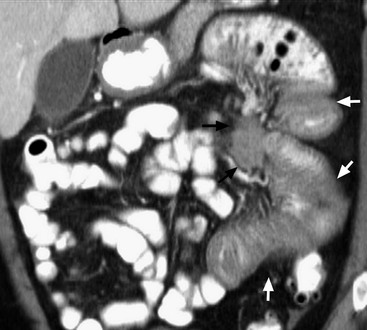

Transmesenteric hernias are increasing in incidence. They are more likely than other hernias to develop volvulus. In children, transmesenteric hernias are the most common type of internal hernia, related to congenital mesenteric defects. In adults, they are usually related to previous surgery, especially Roux-en-Y anastomoses. On CT, a cluster of dilated loops lying adjacent to the abdominal wall, without overlying omental fat lateral to the colon which is displaced centrally, provides an important clue (Fig. 30-3). The mesenteric vascular pedicle is characteristically engorged, stretched and crowded.7